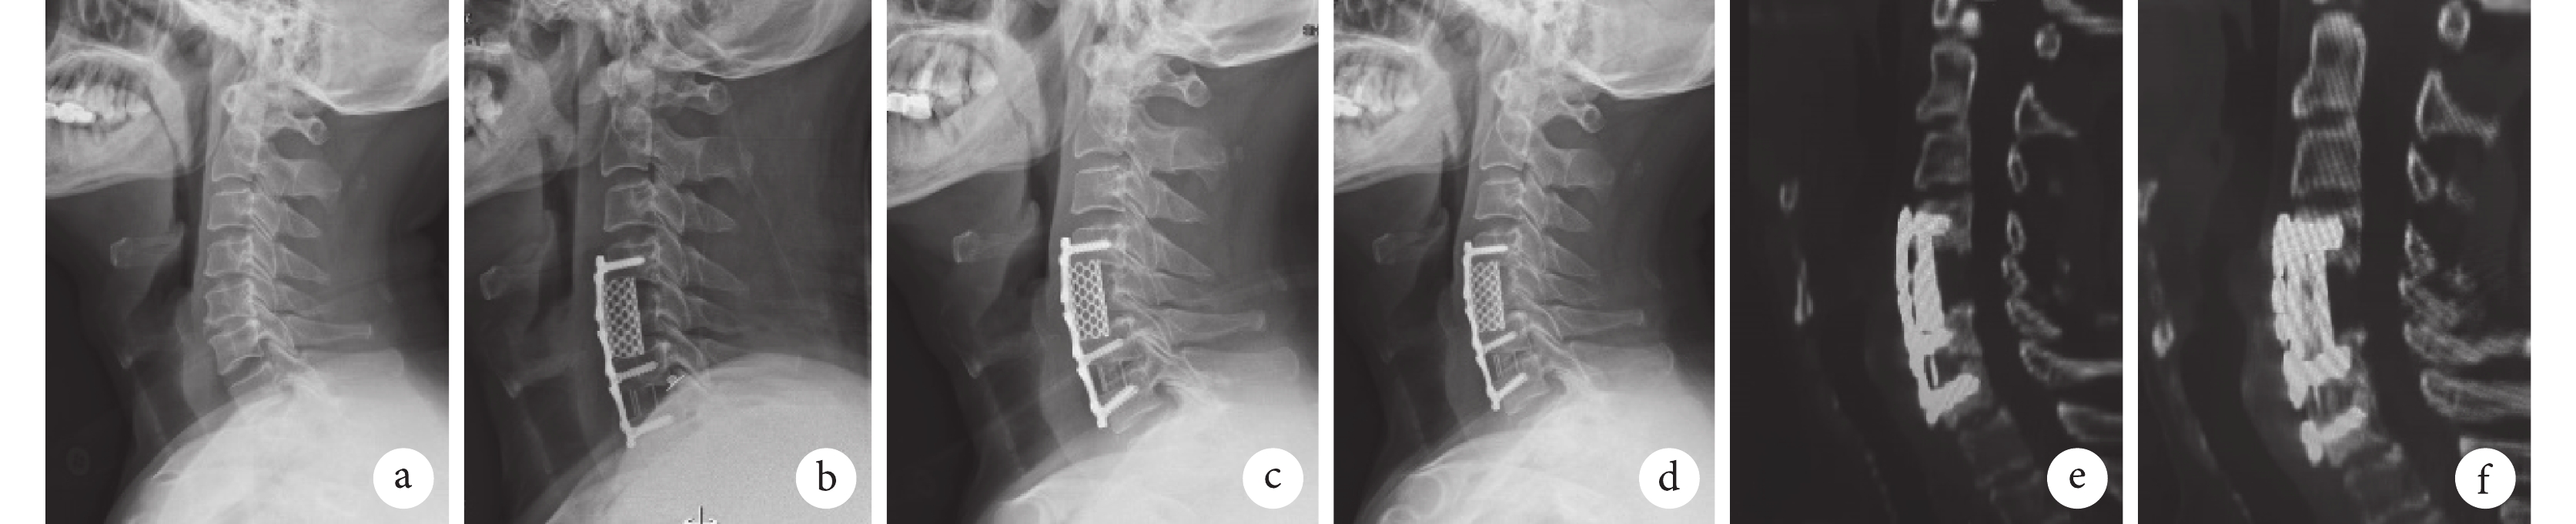

a. 術前 X 線片;b. 術后即刻 X 線片;c. 術后 6 個月 X 線片示植入物沉降不明顯,頸椎曲度尚可;d. 術后 15 個月 X 線片示植入物沉降不明顯,頸椎曲度尚可;e、f. 術后 15 個月 CT 示植入物融合,沉降不明顯

Figure2. A 48-year-old male patient of cervical spondylotic myelopathy at C3-6 in 3D printing groupa. X-ray film before operation; b. X-ray film at immediate after operation; c. X-ray film at 6 months after operation showed that the implant subsidence was not obvious and the curvature of cervical vertebrae was acceptable; d. X-ray film at 15 months after operation showed that the implant subsidence was not obvious and the curvature of cervical vertebrae was acceptable; e, f. CT at 15 months after operation showed that the implant fusion and subsidence was not obvious

3D 打印組手術時間顯著少于 TMC 組,差異有統計學意義(t=3.336,P=0.002);兩組住院時間和術中出血量比較差異均無統計學意義(P>0.05),見表 4。兩組患者均獲隨訪,隨訪時間 12~19 個月,平均 16 個月。兩組術后均未發生明顯并發癥,僅 3D 打印組術后第 2 天出現 1 例反流性咽喉炎,系術中操作引起,1 周內消失。見圖 2、3。